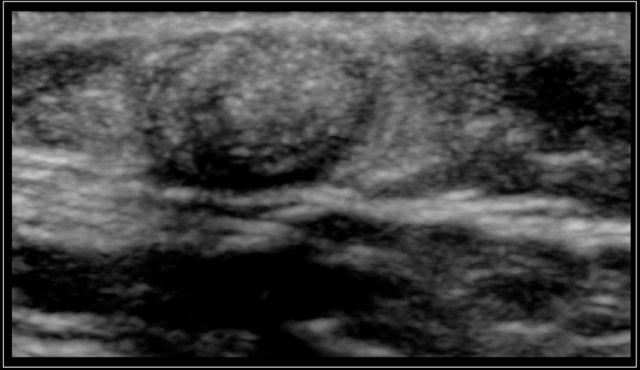

Two-year-old boy with a progressive swelling in the neck. No effect of antibiotics. An atypical Mycobacterium infection (avium) was confirmed. The anechoic parts (arrow) in the node are often seen in atypical Mycobacteria infection.